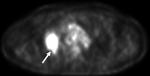

Интересный журнальный случай.

Первоначально эти изменения были расценены, как рак лёгкого.

Последняя иллюстрация - динамика через 14 месяцев.

Кавернозный туберкулёз